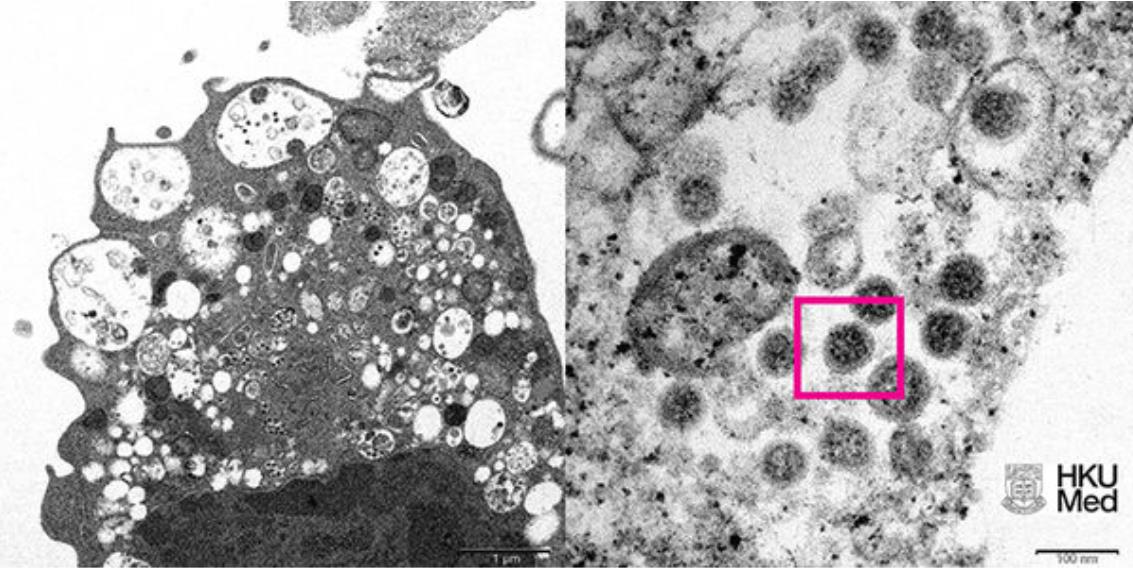

Omicron病毒真实面貌曝光 显微镜下刺突蛋白可见

香港大学公布的Omicron变种病毒显微镜下成像

▲香港大学公布的Omicron变种病毒显微镜下成像。(图/澎湃新闻)

香港大学今(8)日发布新冠变种病毒Omicron在显微镜下的真实面貌,分别为低倍电子显微镜所呈现的感染新型冠状病毒Omicron变种毒株后的猴肾细胞(Vero E6)及高倍电子显微镜下受感染的Vero E6细胞。此外,港大在1日也率先成功从临床标本中分离出Omicron病毒,成为亚洲首个揭开该病毒神秘面纱的团队。

《澎湃新闻》报导,根据港大公布的照片显示,图左照片为低倍电子显微镜下感染新型冠状病毒奥密克戎(Omicron)变异株后的猴肾细胞(Vero E6)。照片显示细胞受损,肿胀囊泡,囊泡内含有黑色小病毒颗粒。显示细胞受损,肿胀囊泡,囊泡内含有黑色小病毒颗粒。

图右照片则为高倍电子显微镜下受感染的Vero E6细胞。照片显示病毒颗粒表面呈现皇冠形的刺突蛋白(红框处)。

此前,香港大学微生物学系团队成功从临床标本中分离出Omicron病毒,为亚洲首个揭开该毒株神秘面纱的团队,有助于开发和生产灭活全病毒疫苗,阻截变种病毒疫情蔓延。